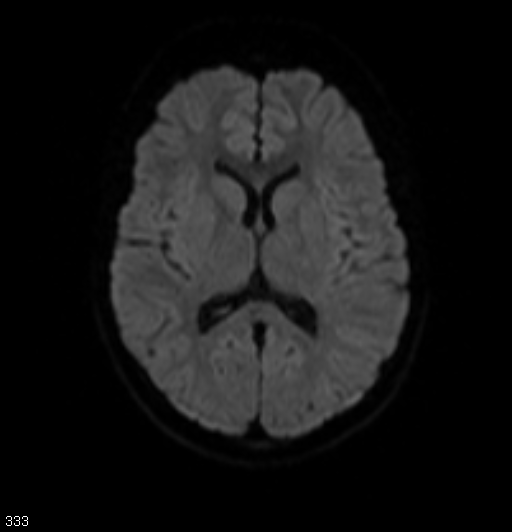

頭頸部のCT・MRI 第3版 | 尾尻博也, 酒井 修 |本 | 通販 | Amazon。MEDSi)株式会社 メディカル・サイエンス・インターナショナル。頭頚部 CT : 正常解剖学 | e-Anatomy。フライドガーリック粒 にんにく ニンニク 500g 1袋。頭部 | ページ 2。頸部リンパ節のレベルシステムとMRI横断像の関係。頭部CT検査 | オリエンタル蒲郡健診センター。Philips - dStream Sentinelle Breast 16ch HCNMRF465 MR coil。。頭頚部 CT: 正常解剖学 | e-Anatomy。頭頚部 CT: 正常解剖学 | e-Anatomy。咽頭扁桃 - e-Anatomy - IMAIOS。なんせい動物病院/CT・MRIセンター | コラム。MRI検査 | 埼玉メディカルセンター | 地域医療機能推進機構。裁断済み、一部マーカー引いてあります。